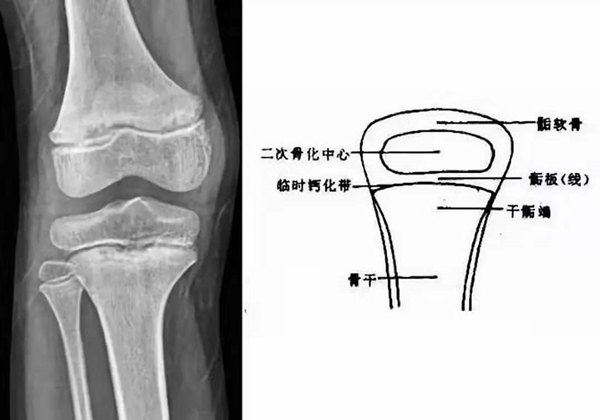

我們都知道,人體的高矮是由骨骼的生長(zhǎng)發(fā)育決定的,特別是下肢長(zhǎng)骨。長(zhǎng)骨呈長(zhǎng)管狀,在長(zhǎng)骨的兩端有一種專(zhuān)管骨骼生長(zhǎng)的骺軟骨,它與干骺端之間有一盤(pán)狀軟骨結(jié)構(gòu)稱(chēng)為骺板(線),在幼兒的X光片上表現(xiàn)為一條較寬的透光帶。 (見(jiàn)下圖)

未成年時(shí)隨著年齡的增加骺軟骨端不斷骨化,骨骼就不斷增長(zhǎng)。當(dāng)骨骺線完全閉合時(shí)骨骼就停止生長(zhǎng),個(gè)子也就不再增長(zhǎng)了。一般骨骺端完全閉合的年齡是18~20歲左右。